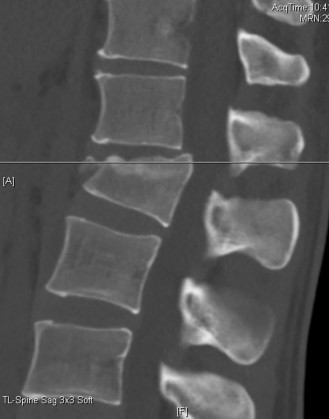

Figure 1–25

Figure 1–26

The correct answer is (B). The images demonstrate an L1 vertebral body fracture with a small degree of kyphosis. There is comminution of the vertebral body with a posterior vertebral body fragment that is slightly retropulsed into the spinal canal. This separate posterior vertebral body fragment (which is noncontiguous with the pedicles) is the hallmark of a burst fracture. Compression fractures do not have any posterior vertebral body involvement. A Chance fracture, also known as a seat belt fracture or flexion–distraction injury, will exhibit distraction of the posterior elements through bone, bone-ligament, or purely ligament structures, with an axis of rotation somewhere within the anterior vertebral body or anterior to the vertebral body. A fracture dislocation exhibits translational deformities between the injured levels. While there appears to be a translational deformity on the sagittal CT, the vertebral bodies of the uninjured levels above and below are actually well aligned.